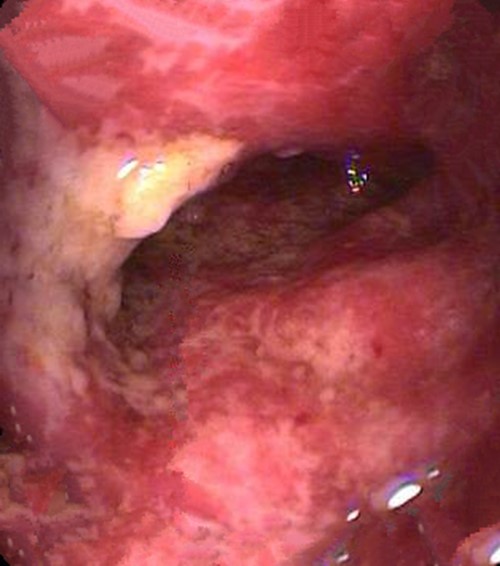

纖維結腸鏡檢查

慢性結腸炎圖片

嚴重慢性結腸炎的

嚴重慢性結腸炎腐爛的